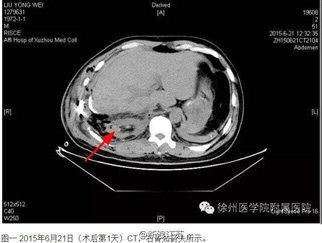

就在网上骂声一片的时候,事情在55日下午发生了转机——5日下午,徐州医学院附属医院针对此事件发表声明,称该报道内容严重失实,并附有两张术后CT复查均显示右肾存在。并有新闻爆出,刘永伟向医院提出索赔200万的消息,并得到本人证实,这颗被找到的肾,和天价的索赔款,又掀起了舆论的一阵哗然。

此次徐附院能翻案的关键证据,就是患者术621日和625日为了评估病情变化做的两次CT,发现右肾都在。